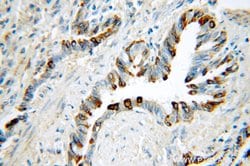

This antibody is specifically against KRT7.

| Immunocytochemistry, Immunofluorescence, Immunohistochemistry (Paraffin), Immunoprecipitation, Western Blot | |